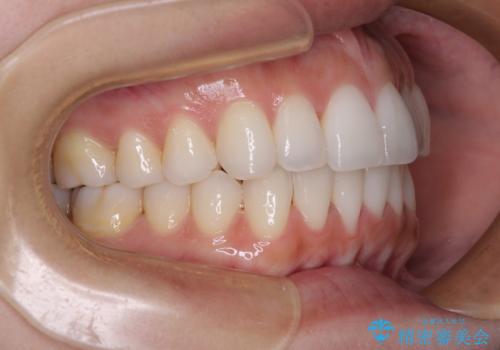

前歯のクロスバイト インビザラインによる矯正治療

- 上下のクロスバイトと前歯のデコボコを気にして来院された患者様です。

インビザラインを用い、IPR(歯と歯の間を削る)と歯列全体を拡大させることで、歯並びを整えていくこととしました。

治療を急いでいらっしゃらなかったため、のんびりと治療を進めていきました。3年以上の期間を要しましたが、きれいな口元に仕上がりました。